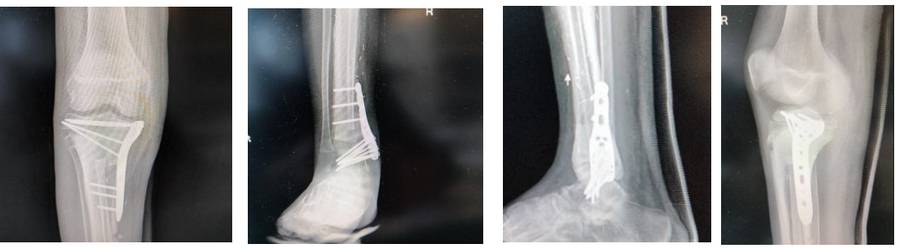

Ameliyat Sonrası: Röntgende anatomik plak ile proksimal osteotomi hattının fiksasyonu ve ayak bileğine artrodez işlemi görülmekte